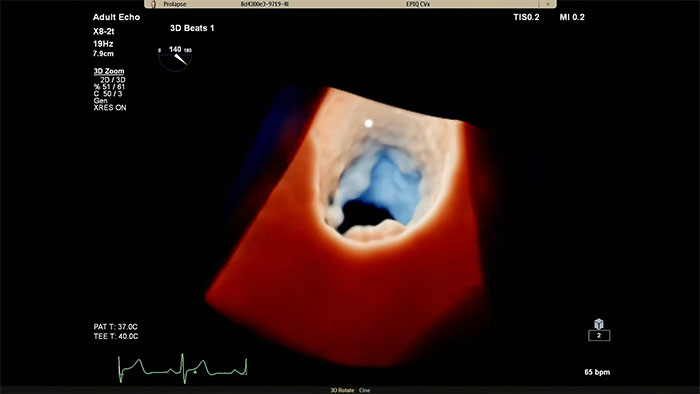

Philips Cardiac TrueVue on EPIQ CVx.

View enhanced visualizations of structures and flow with TrueVue Color

Visualize cardiac morphology using ultrasound with TrueVue Glass